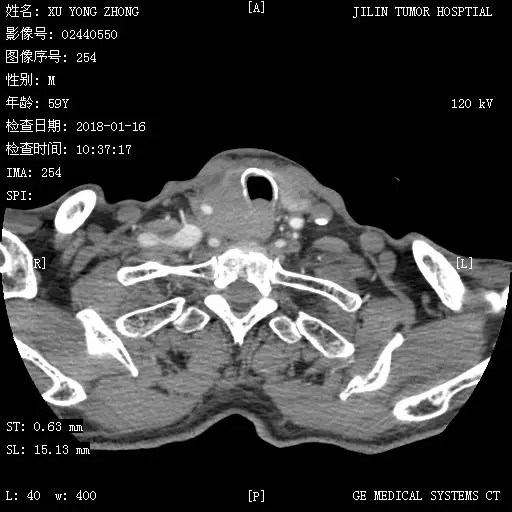

该患者因下咽癌,行双侧颈部淋巴结清扫术,右侧梨状窝鳞状细胞癌切除术,下咽成型术一年余。放射治疗后复发,出现进食受限,并呈持续性加重。来我院以“下咽癌术后放疗后复发”收入耳鼻咽喉头颈外二科。入院后病情逐渐加重,已不能饮水三天。经耳鼻咽喉头颈外二科与放射线科会诊,决定给予CT引导下胃造瘘术,以解决不能经口进食问题。

术前经过与介入科及ICU科会诊,决定先由介入科在DSA引导下胃腔放置营养管,用于术中注入气体,充盈胃腔。再于CT引导下进行胃穿刺造瘘。